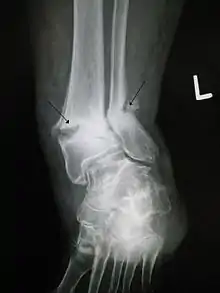

| Bone fracture | |

| Other names | broken bone, bone break |

| Internal and external views of an arm with a compound fracture, both before and after surgery | |